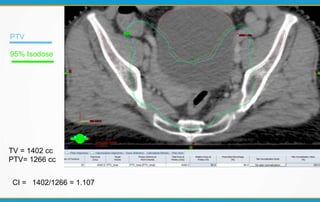

Dose Conformity

 Characterizes the degree to which the high dose region

conforms to the target volume, usually the PTV.

CI = TV / PTV

CI – must be between 1 – 2

CI of 0.9 – 1 & 2 – 2.5 means minor violation

CI of < 0.9 & > 2.5 means major violation

TV = 1402 cc

PTV= 1266 cc

CI = 1402/1266 = 1.107

PTV

95% Isodose